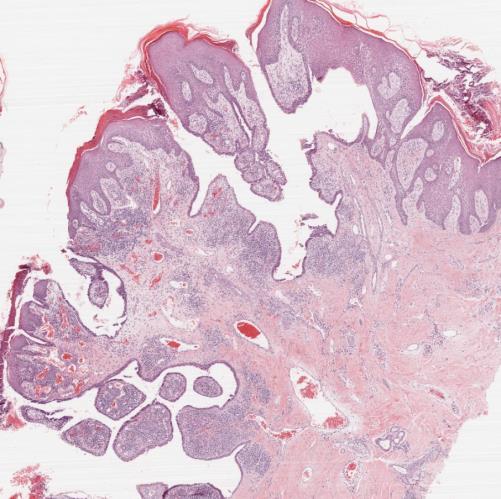

• Syringocystadenoma papilliferum

• Benign apocrine neoplasm

• Isolated or in association with naevus sebaceous

• Endophytic crateriform proliferation with papillary architecture